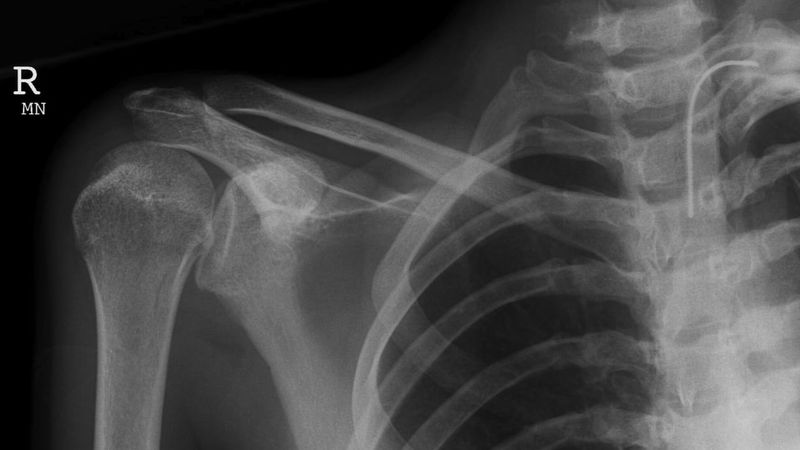

- Chụp X-quang: giúp xác định các tổn thương ở xương thuộc khớp vai, thường là sau tai nạn.

X-quang là một xét nghiệm hình ảnh quan trọng trong chấn thương